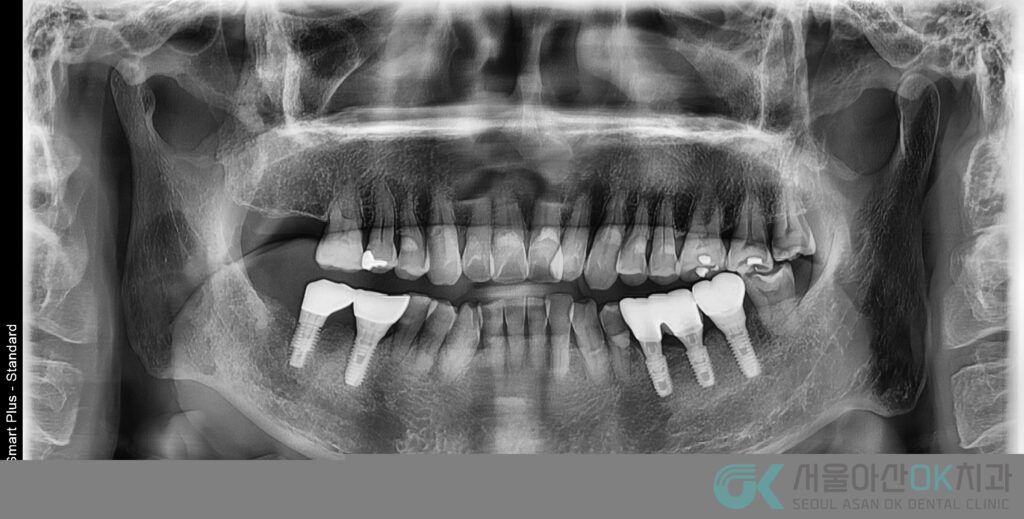

또한 파노라마 평가에서

전반적인 만성 치주염(수평적 골 소실) 소견이 함께 확인되어,

“임플란트만 심으면 끝”이 아니라 잇몸 컨디션을 안정화하면서 임플란트를 진행하는 장기 플랜이 필요했습니다.

진단 및 검사: 파노라마·교익·CT 기반으로 “심을 수 있는 자리”를 확인

파노라마 촬영: 전악 치주 상태(골 소실 양상) 확인

교익 촬영: 인접면 우식 여부 확인

임플란트 진단(CT Taking 메모): #46 부위의 골량/골폭, 식립 가능 위치 확인

을 통해 “어디까지 뼈가 남아 있고, 뼈이식이 필요한지”를 먼저 판단했습니다.

핵심은 #46 부위가 단순 결손이 아니라,

기존 치주 상태와 골 소실이 동반되어 식립과 동시에 간단 GBR(골유도재생술)이 필요하다는 점이었습니다.